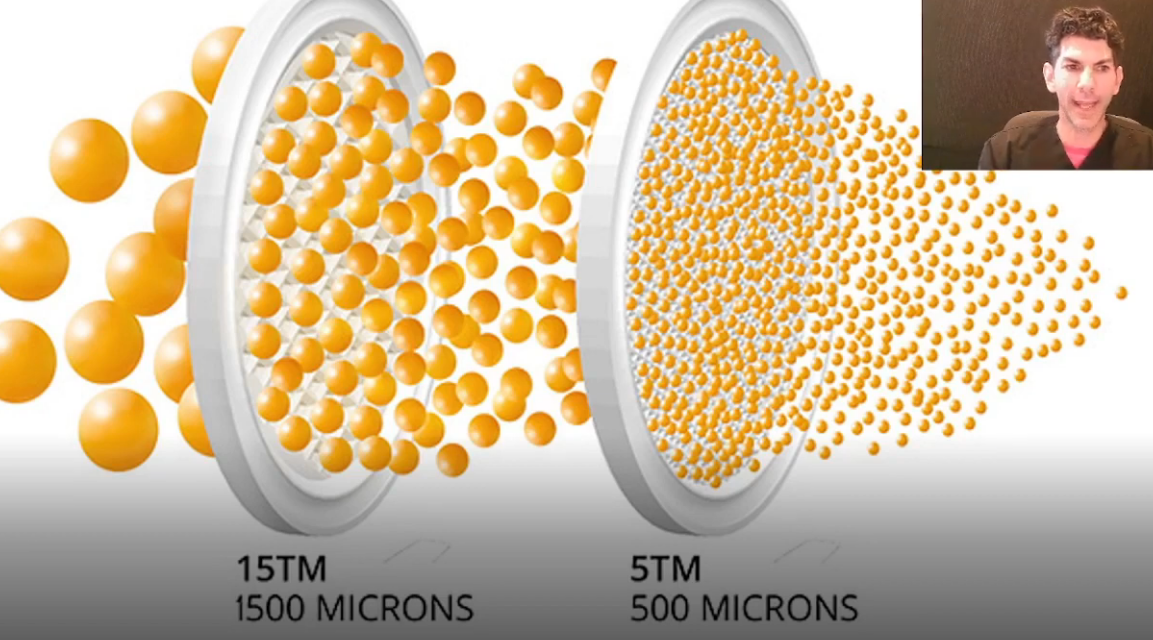

When fat is harvested, it comes in different sizes, and the sizes matter depending on where the fat is placed. Through filtering, we’re able to separate out debris and damaged tissue, but this also results in fat being divided into smaller or larger clusters.

Smaller clusters of fat are better for delicate areas like the lips & undereyes (which we’re dealing with), where the skin is thinner and uneven texture is much more noticeable if you place large clusters of fat too superficially. Smaller fat clusters spread more evenly, integrate more smoothly with surrounding tissue, and have an easier time receiving oxygen and nutrients early on.

A filter like this one is placed between two syringes, then filtered through around 10-15 times to achieve the micron size needed.

When fat is harvested, it comes in different sizes, and the sizes matter depending on where the fat is placed. Through filtering, we’re able to separate out debris and damaged tissue, but this also results in fat being divided into smaller or larger clusters.

Smaller clusters of fat are better for delicate areas like the lips & undereyes (which we’re dealing with), where the skin is thinner and uneven texture is much more noticeable if you place large clusters of fat too superficially. Smaller fat clusters spread more evenly, integrate more smoothly with surrounding tissue, and have an easier time receiving oxygen and nutrients early on.

A filter like this one is placed between two syringes, then filtered through around 10-15 times to achieve the micron size needed.